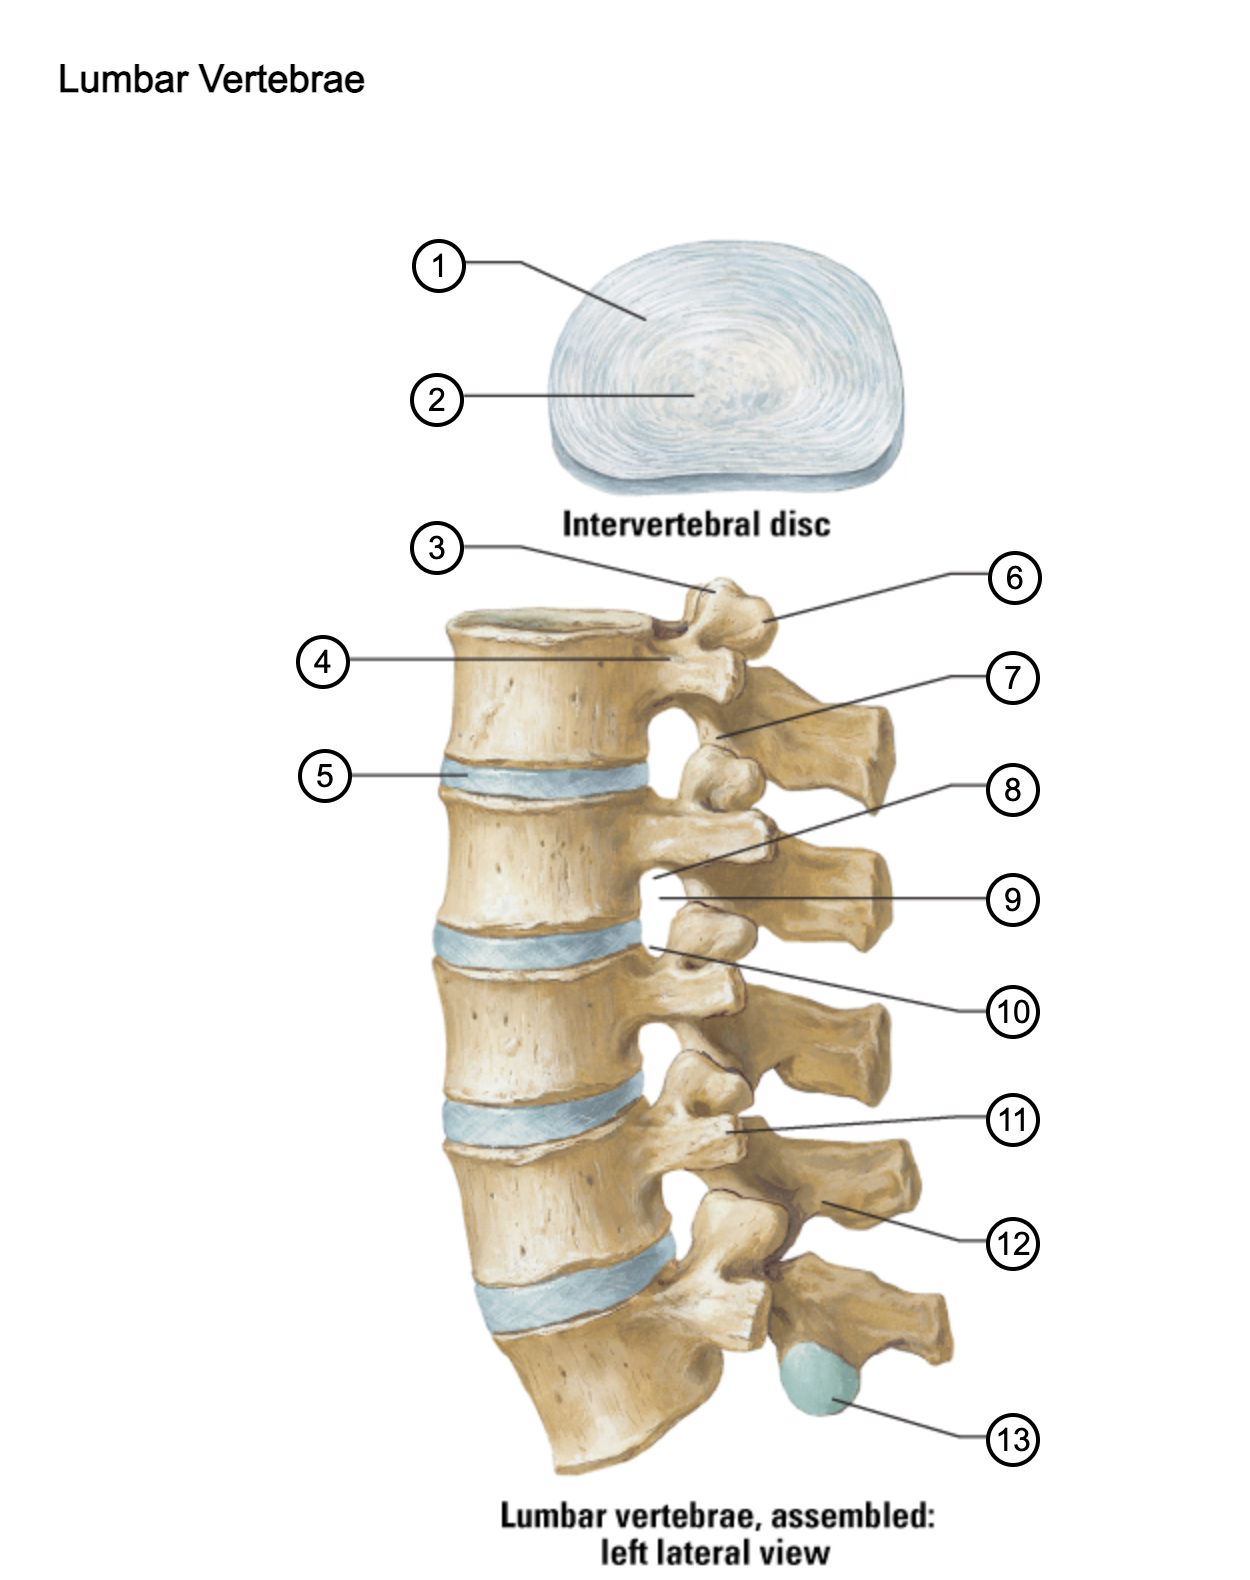

1

anulus fibrosus

2

nucleus pulposus

3

superior articular process

4

pedicle

5

intervertebral disc

6

mammillary process

7

inferior articular process

8

inferior vertebral notch

9

intervertebral notch

10

superior vertebral notch

11

transverse process

12

lamina

13

inferior articular facet